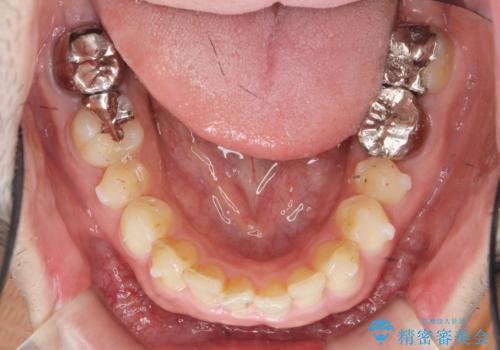

ディープバイトのマウスピース矯正

- 飛び出してしまい、隙間のある前歯をきれいに並べたい、と矯正治療を希望され来院されました。

上顎前歯を後方に引き、隙間を閉じるためには下顎前歯の絶対的な圧下を行い、深い噛み合わせを改善することが必要です。

圧下は歯の動きの中でも難しい動きの一つで時間がかかることが多いです。

前歯でチューイーをしっかり噛み、咬合圧を伝えたことで下顎前歯が圧下し、上顎前歯の隙間を閉じることができました。